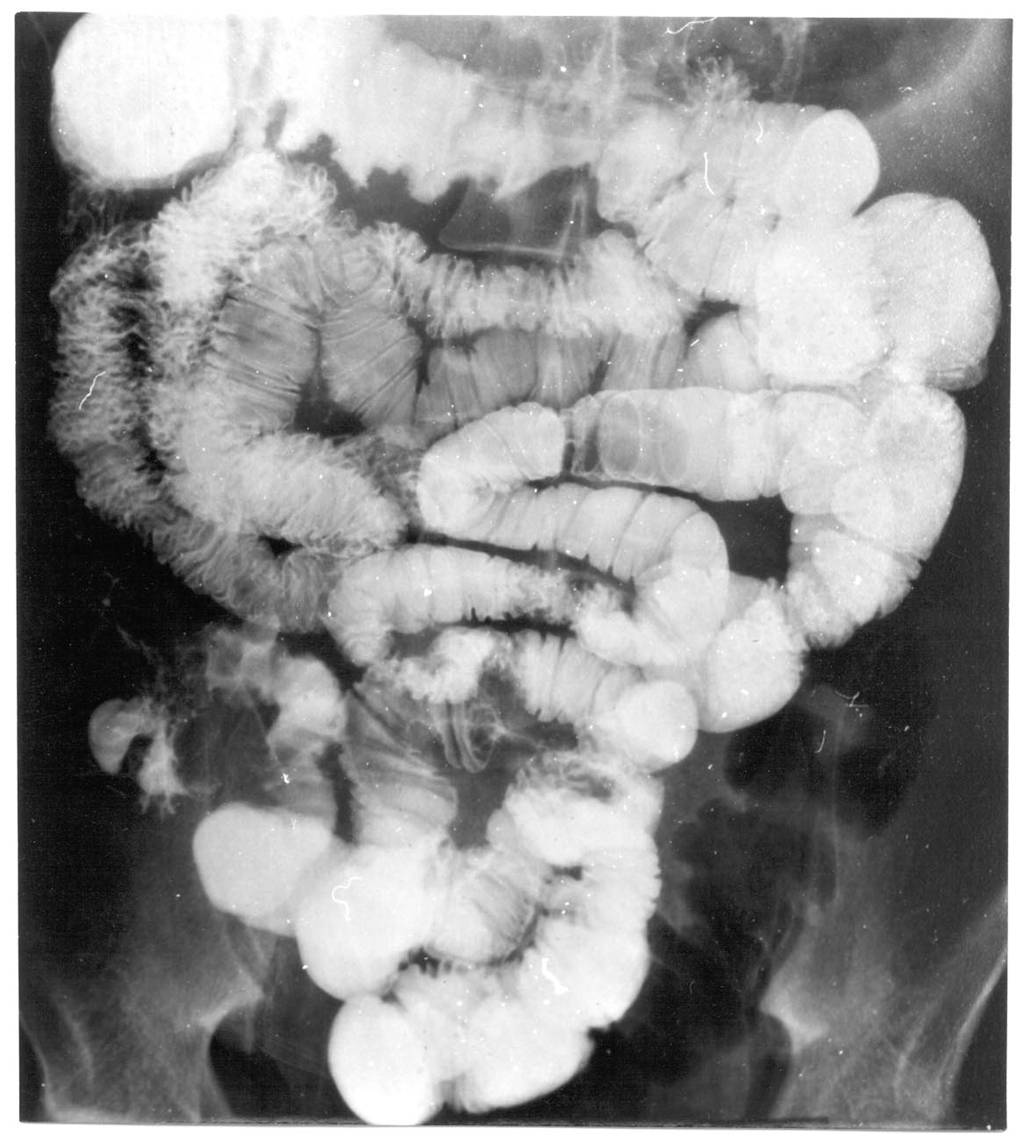

Image

Fig.21.: Radiograph of selective enterocylsis